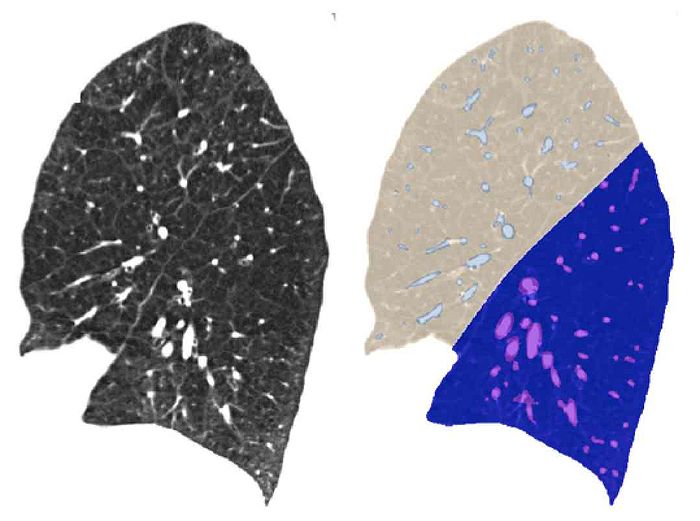

The Chest Imaging Platform provides automatic tools for lung lobe segmentation. These rely in part on detecting pulmonary fissures, which can be difficult due to poor signal-to-noise ratios and/or lung pathologies.

• Use positive and negative examples of fissures to train a classifier that can be used to detect/enhance fissures

• Guided by approach described in van Rikxoort et al: 'Supervised enhancement filters: application to fissure detection in chest CT scans'